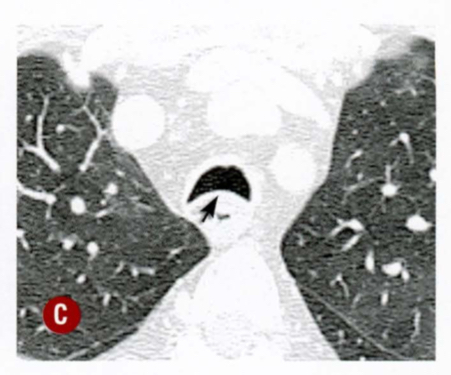

Qual alteração traqueal?